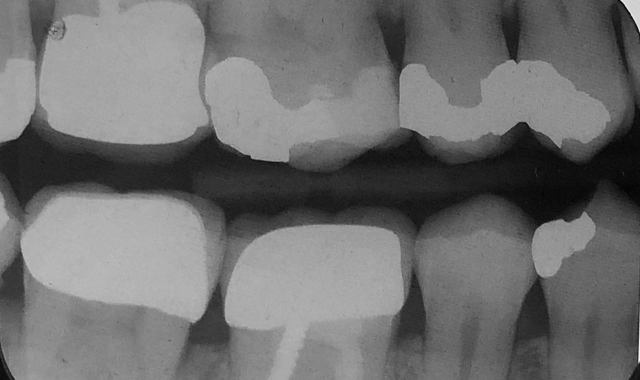

A 60-year-old male patient presented complaining of pain from the lower right first molar. Upon clinical examination, tooth #30 was sensitive to percussion and had a fractured disto-occlusal-lingual amalgam.

After discussion with the patient and effective local anesthesia, the existing amalgam was removed to reveal caries extending into the pulpal tissue (Fig. 1).

The patient was referred for root canal therapy and after three weeks returned for a restoration (Fig. 2). The tooth was cleaned of temporary restorative material and was prepared for a post and core. A Dentatus Classic Surtex® (Dentatus) metal post was cemented with self-adhesive resin cement (TotalCem, Itena) and an adhesive layer of CLEARFIL SE Bond (Kuraray Dental) was placed as per manufacturer’s instructions, followed by light curing for 10 seconds.